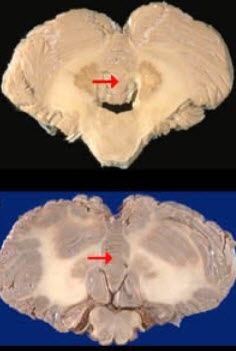

如图箭头所示为小脑哪个部位( )

A:小脑上脚

B:小脑下脚

C:小脑蚓部

D:小脑扁桃体

E:小脑中脚